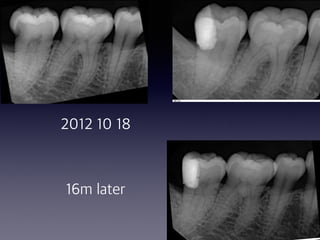

2012 10 18

16m later